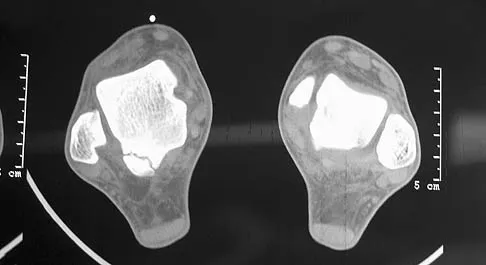

Figures 1a through 1c show the radiograph and MRI scans of a 16-year-old patient who has a painful hip. Examination reveals a significant limp, limited abduction and internal rotation, and severe pain with internal rotation and adduction. A biopsy specimen is shown in Figure 1d. What is the deposited pigment observed in this condition?

Explanation

Pigmented villonodular synovitis (PVNS) is a synovial proliferative disorder that remains a diagnostic difficulty. The most common clinical features are mechanical pain and limited joint motion. On radiographs, the classic finding is often a large lesion, associated with multiple lucencies. Other findings may include a normal radiographic appearance, loss of joint space, osteonecrosis of the femoral head, or acetabular protrusion. MRI is the imaging modality of choice and will show the characteristic findings of a joint effusion, synovial proliferation, and bulging of the hip. The synovial lining has a low signal on T1- and T2-weighted images, secondary to hemosiderin deposition. Copper deposition occurs in patients with Wilson's disease, which mainly affects the liver. Bhimani MA, Wenz JF, Frassica FJ: Pigmented villonodular synovitis: Keys to early diagnosis. Clin Orthop 2001;386:197-202.